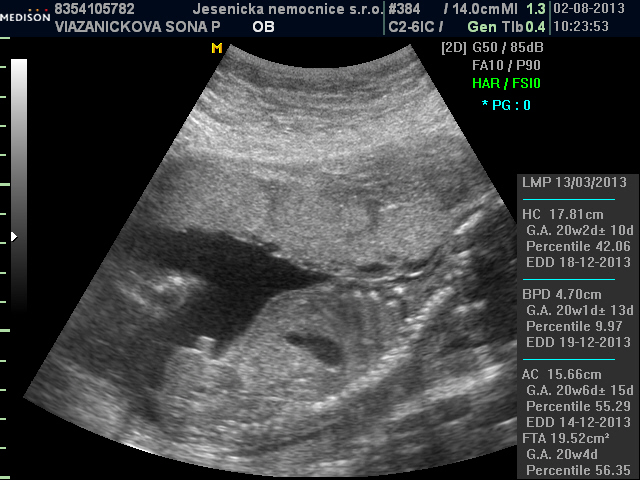

Ahoj holky, hlásíme se z velkého UTZ. Tak po těch strastech ze screeningu a návštěvě genetiky hlásíme, že jsme na 99 % OK a že čekáme holčičku Barunku po mně

. Konečně si začnu užívat, do teď člověk nevěděl, jak to vše dopadne. Nyní mám energie na rozdávání a žádné potíže, proti těm problémům na začátku těhu, tak doufám, že to ještě dlouho vydrží. Barče držíme pěsti ať vše dopadne OK.